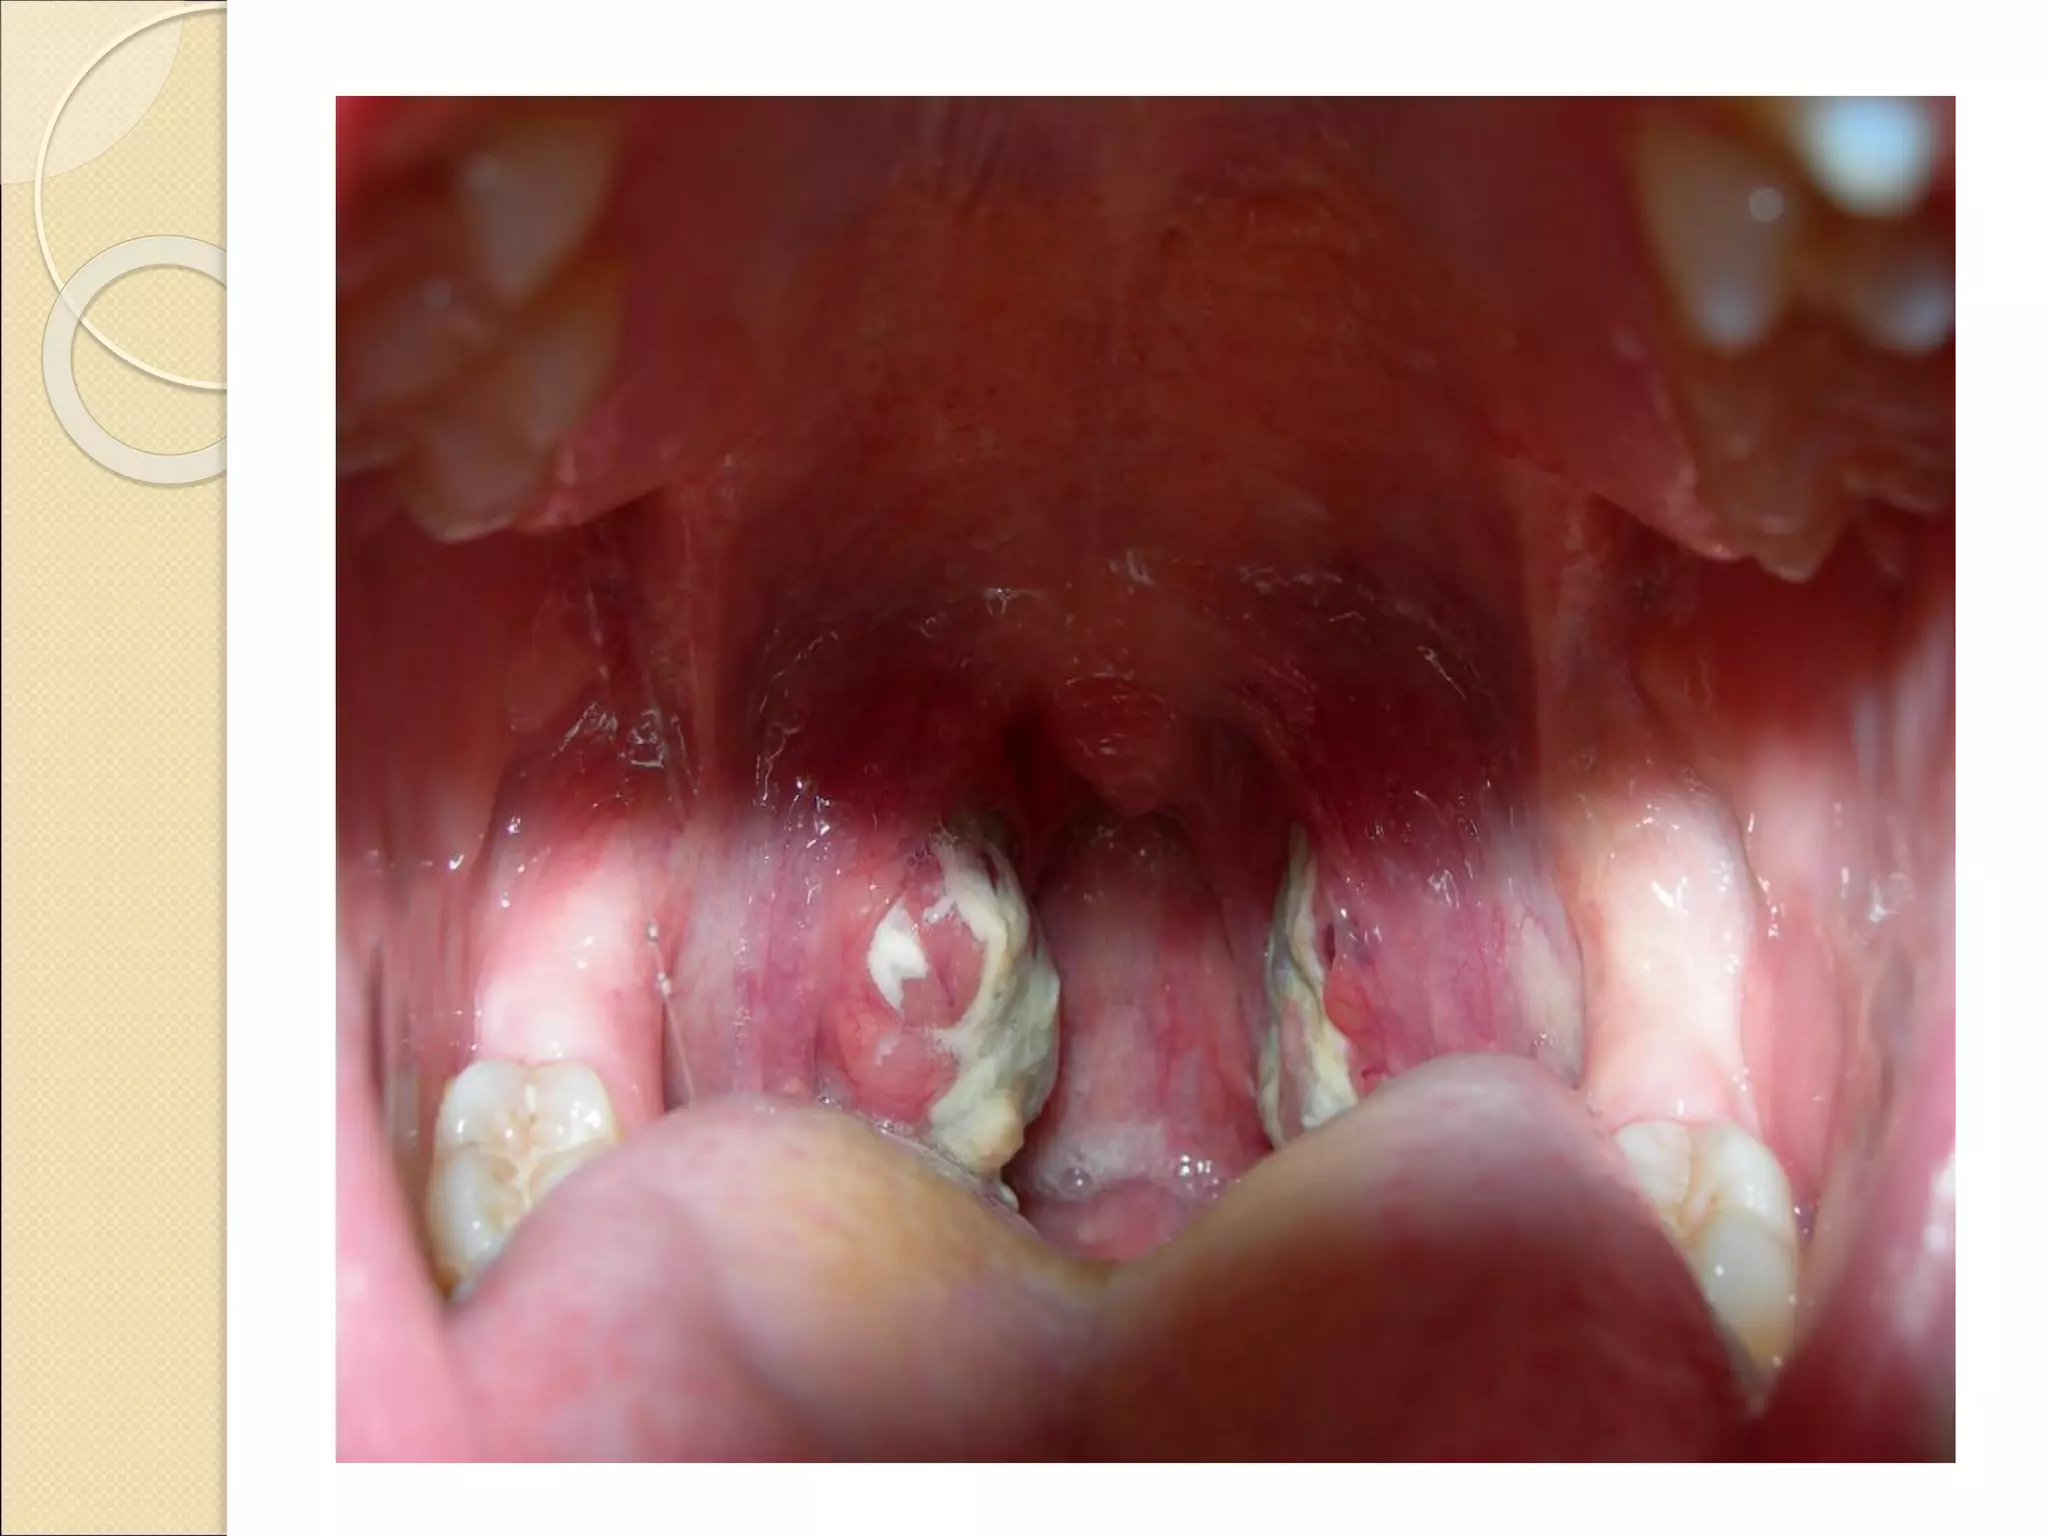

Ангина-острая инфекционная болезнь с воздушно-

капельным механизмом передачи,

характеризующаяся поражением лимфоидной

ткани ротоглотки и проявляющаяся общей

интоксикацией,болями в горле и увеличением

поднижнечелюстных лимфатических узлов.

Возбудителем стрептококковой ангины является

Streptococcus pyogenes. Среди бактерий является

самым часто встречающимся возбудителем

ангин. Также возбудителями бывают стрептококки

группы G и C.

Ангина-острая инфекционная болезньс воздушно- капельным механизмом передачи, характеризующаяся поражением лимфоидной ткани ротоглотки и проявляющаяся общей интоксикацией,болями в горле и увеличением поднижнечелюстных лимфатических узлов. Возбудителем стрептококковой ангины является Streptococcus pyogenes. Среди бактерий является самым часто встречающимся возбудителем ангин. Также возбудителями бывают стрептококки группы G и C.